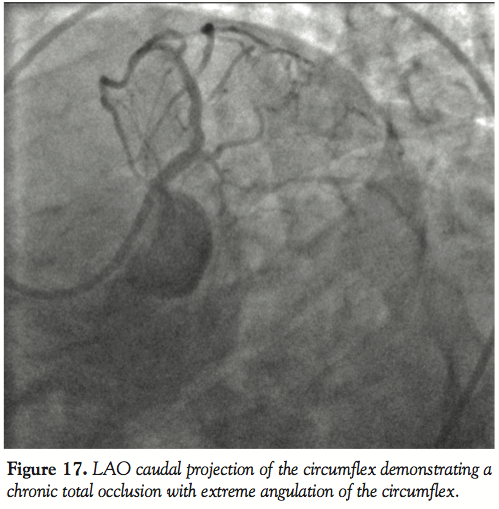

Case 6. This case demonstrates the utility of the GuideLiner catheter in coaxial alignment for delivering stents even in very proximal coronary segments because of difficulties related to extreme proximal vessel tortuosity. An extremely angulated take off of the left circumflex artery off the left main coronary artery was dealt with by placing a GuideLiner catheter into the distal left main. Even though the GuideLiner did not actually enter the circumflex artery, it provided enough support for the delivery of a drug-eluting stent to treat the entire proximal stenosis successfully with one stent (Figures 17–19).

Another situation where the GuideLiner finds utility in coronary intervention is in the setting of proximal vessel tortuosity illustrated in case 6. In this case, the extreme angulation of the origin of the circumflex artery from the left main artery made it impossible to advance the stent past the proximal vessel even after straightening out the proximal vessel with stiff coronary guidewires and with deep engagement of the guiding catheter. The soft atraumatic tip of the GuideLiner catheter allowed delivery of stents relatively easily after negotiating the proximal bend of the vessel. This can greatly shorten the case and fluoroscopy times and minimize contrast load to the patient.